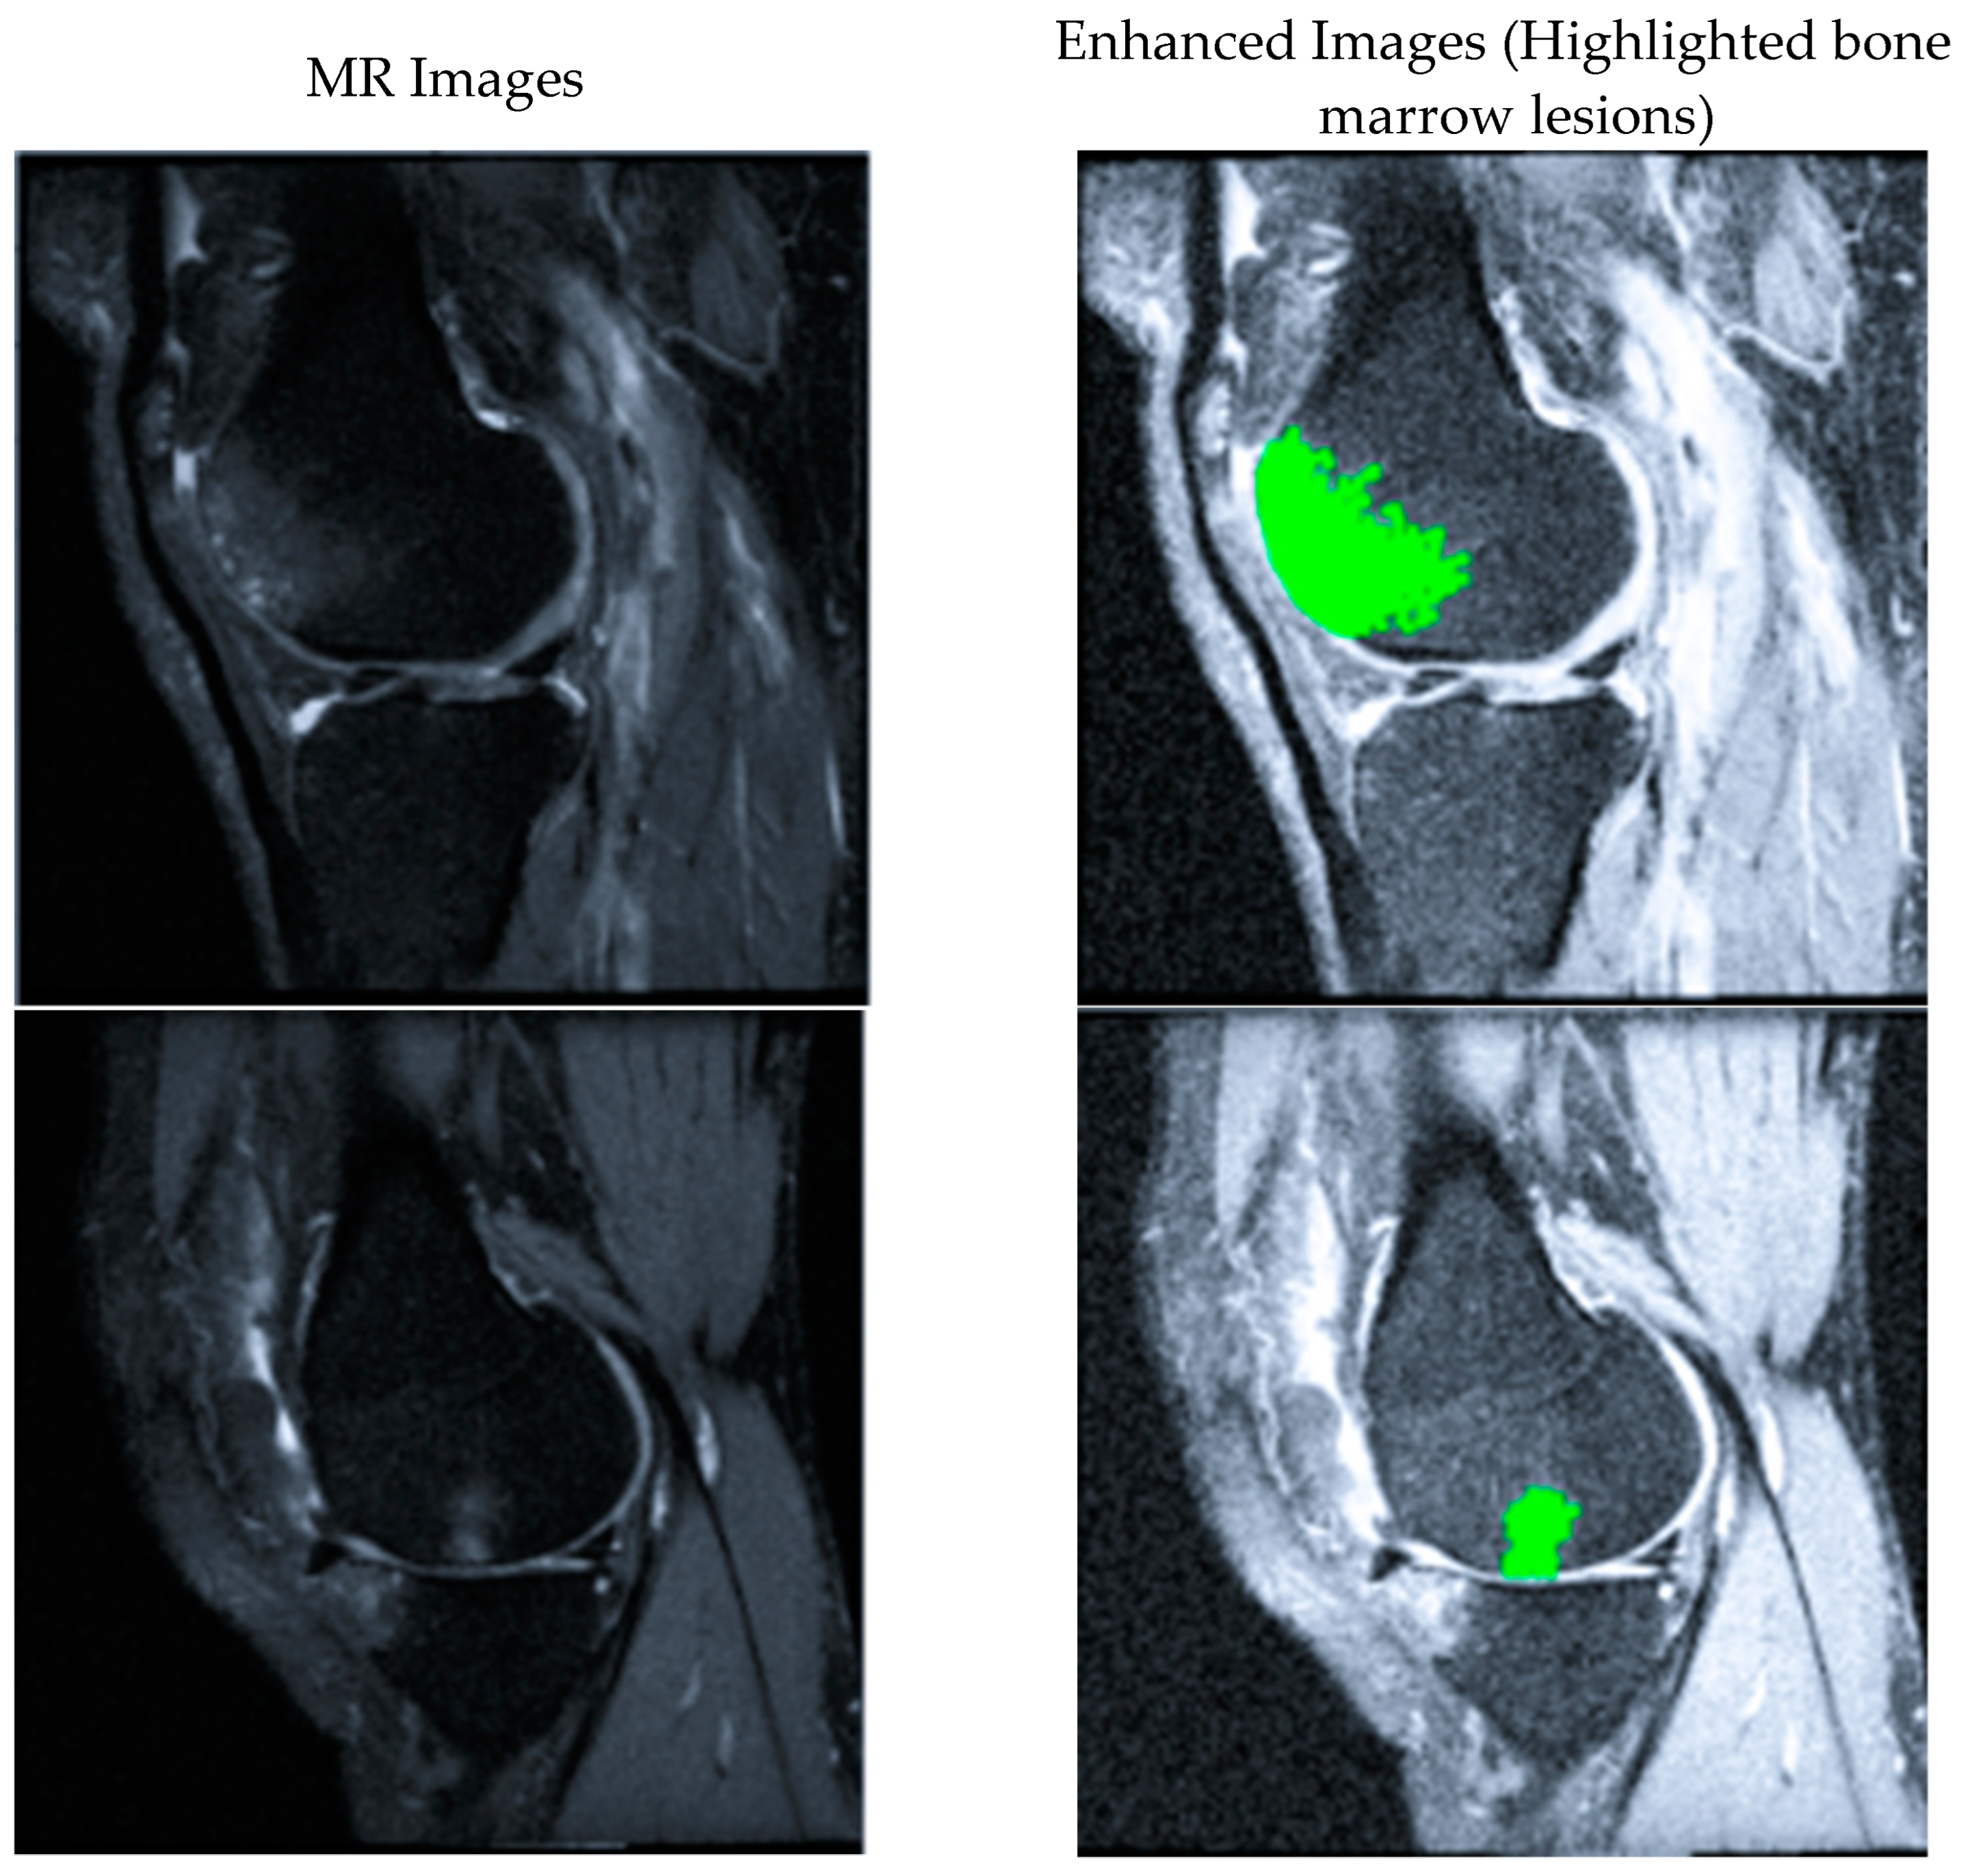

Automatic Segmentation of Bone Marrow Lesions on MRI Using a Deep Learning Method

Abstract

1. Introduction

2. Methods